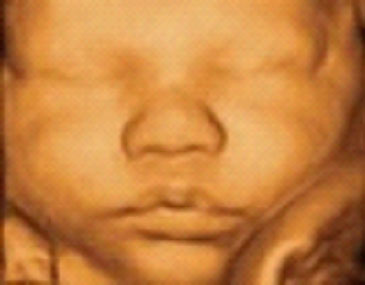

Best Week For 3d Ultrasound

Images of Best Week For 3d Ultrasound

Best Week For 3d Ultrasound Pictures

Pictures of Best Week For 3d Ultrasound

Photos of Best Week For 3d Ultrasound

Ultrasound: Past, Present and Future K. Kirk Shung ultrasound scanners are capable of producing images of ana- Fig. 3 A 3D image of a 10-week old fetus in utero (courtesy of Philips) Fig. 4 B-mode image (left) ... Doc Viewer

Baby Lewis 4D Ultrasound At 11 weeks 3 Days - YouTube

Twin 3D Ultrasound - 21 weeks 3 Days - AMAZING!!! - YouTube